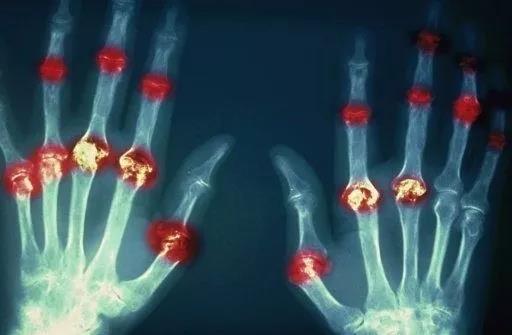

? 類風濕關節(jié)炎

類風濕關節(jié)炎是一種高度致殘的自身免疫性疾病,發(fā)病十年的患者中至少有50%的人失去勞動能力。

類風濕關節(jié)炎©Health Same of Flickr

1977年,Baldwin在用骨髓干細胞移植治療再生障礙性貧血的過程中,意外發(fā)現(xiàn)患者的類風濕關節(jié)炎得到緩解。

2004年,歐洲骨髓移植和抗風濕病聯(lián)盟對60例類風濕病關節(jié)炎移植患者進行回顧性分析,這些患者的關節(jié)破壞都達到不可修復程度,生活不能自理,通過干細胞移植治療后,67%的患者得到明顯緩解。

我國國內多家醫(yī)院已開展了干細胞治療類風濕性關節(jié)炎的臨床研究。首例自體干細胞移植治療類風濕關節(jié)炎在北京協(xié)和醫(yī)院完成。經過5個月隨訪,這些經常規(guī)藥物治療失敗且病情發(fā)展迅速的患者,在接受干細胞移植治療后,癥狀均獲得改善,關節(jié)腫脹消失,各項檢查指標恢復正常。

解放軍323醫(yī)院2011年的一項臨床研究中,27位患者(對照組)只使用藥物治療;另外153位患者(細胞治療組)在藥物治療的基礎上進行臍帶間充質干細胞輸注。結果顯示,治療組DAS28、HAQ 評分、ACR20較對照組下降明顯(分值越低,療效越好),Th1/Th2趨于平衡、Treg升高與臨床實驗指標及癥狀的緩解直接相關。